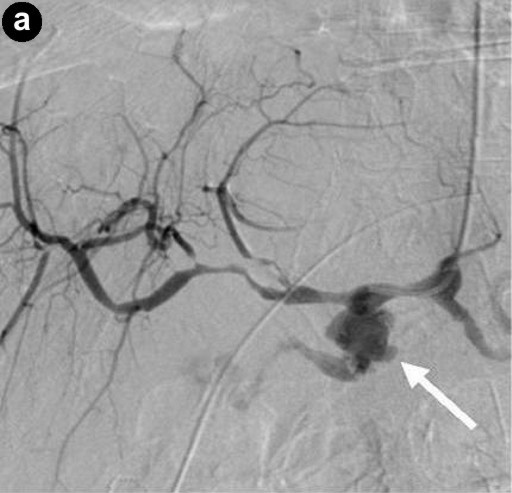

The sites of haemorrhage, management and outcome are summarised in Table 1. All PPH were classified by us as ISGPS type C. The initial CT angiogram revealed the source of the bleeding in all patients and 6 patients went on immediately to have mesenteric angiography. Stent grafting (n=2) was used to control bleeding sites in the common hepatic artery (Figure 1) and coil embolisation (n=5) was employed for bleeding sites arising from branches of superior mesenteric artery, gastroduodenal artery and splenic artery (Figure 2). One patient who underwent metal coil embolisation of proximal hepatic artery for a large psuedoaneurysm from the stump of gastroduodenal artery required further coil packing of the vessel and a follow-up CT scan two weeks after the initial embolisation demonstrated persistent flow in the common hepatic artery. No laparotomy was ever needed after embolization.

Figure 1. Digitally subtracted angiographic images. a. A pseudoaneurysm arising from the stump of the gastroduodenal artery (arrowed). The tip of the catheter is in the common hepatic artery. b. Image from the same patient after deployment of a 6x20 mm stent-graft (arrowed) in the common hepatic artery across the origin of the gastroduodenal artery. The stent-graft has excluded flow from the gastroduodenal stump. The tip of the catheter is in the common hepatic artery. |